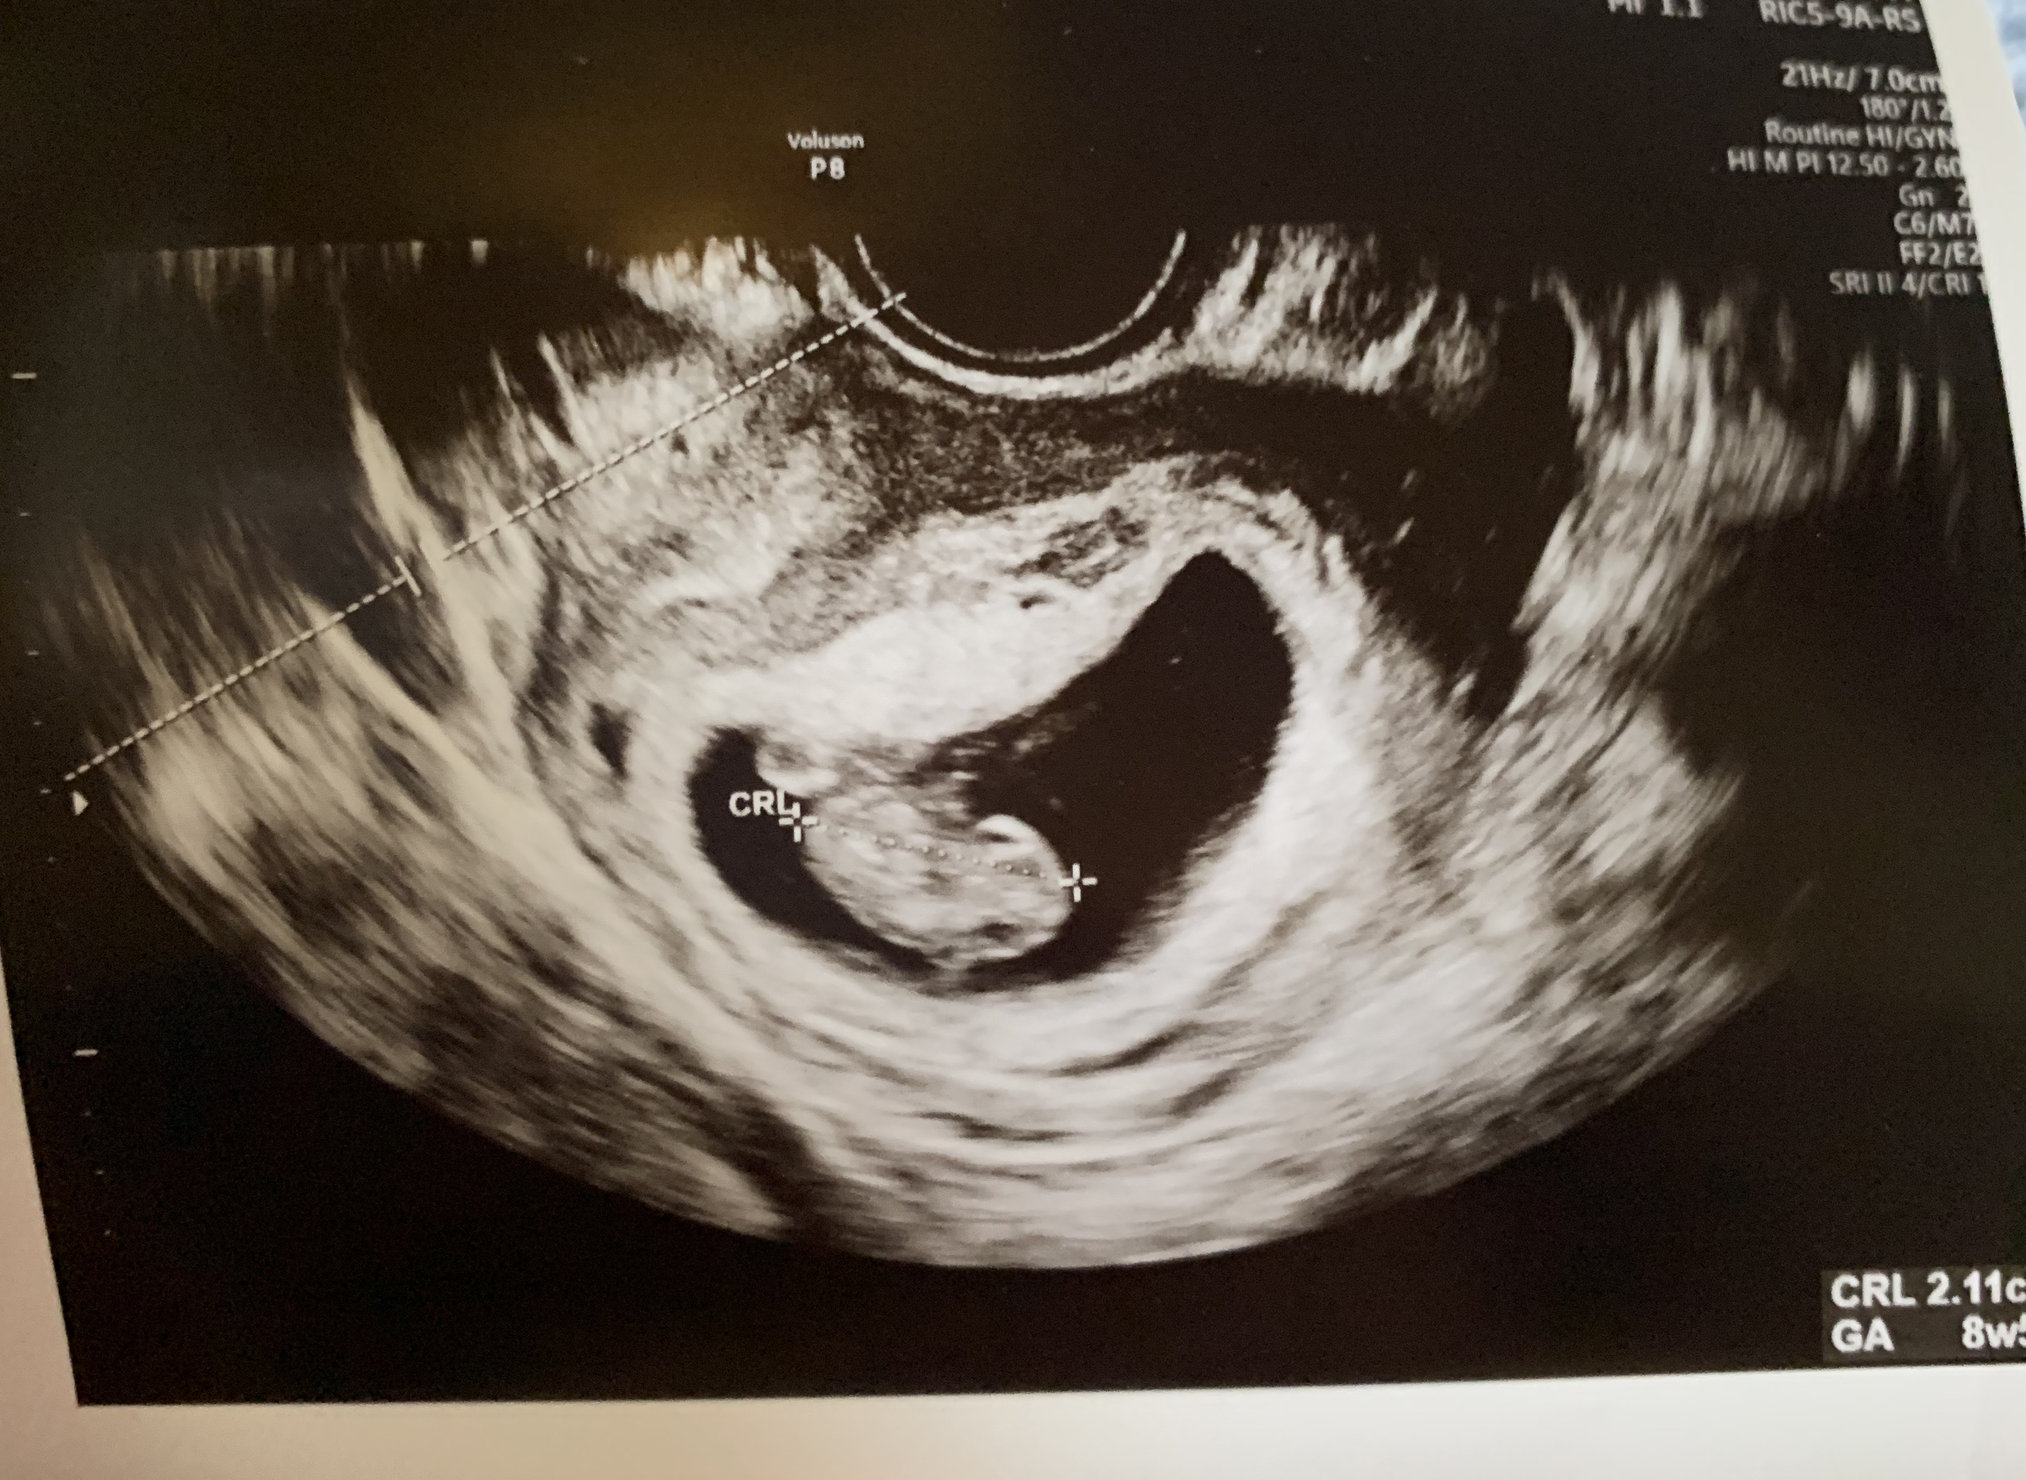

6w1d HB: 111 ♥️ little blob